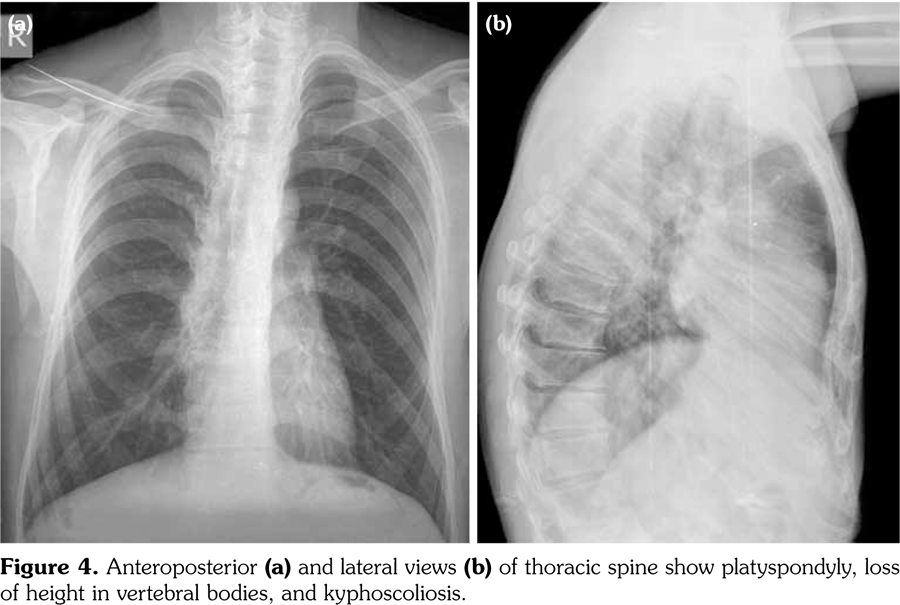

Physical examination revealed decreased range of motion in shoulders, wrists, metacarpophalangeal, proximal IP, distal IP, and ankle joints. In particular, the IP, metacarpophalangeal and metatarsophalangeal joints had bony enlargements, mild tenderness and flexion contractures; however, no signs of inflammation like redness, effusion, or other signs of synovitis (Figure1). The patient also had mild spinal scoliosis, significant thoracolumbar kyphosis, and pectus excavatum deformity. Furthermore, he had saddle nose deformity, bilateral floppy pinna and audiovestibular dysfunction (sensorineural hearing loss and tinnitus) (Figure 2). The rest of the systemic examination was unremarkable.

Radiographs of the hands showed enlargement of metaphyses, flattening of epiphyses, and narrowing of joint spaces with no erosions. Lateral radiograph of the foot revealed bilateral large ossified trigonum attached to the talus (mega os trigonum) (Figure 3). Radiographs of the spine showed increased kyphosis, generalized platyspondyly particularly at the thoracolumbar junction, and irregularity of the vertebral end- plates (Figure 4). Magnetic resonance imaging of thoracolumbar spine demonstrated irregularity in vertebral end-plates, multiple disk herniations, and platyspondyly (Figure 5). Dynamic contrast- enhanced magnetic resonance imaging of the wrist did not reveal any signs of synovial inflammation.

Clinical features of PPD have been described in several reports.(9-11) The radiographic features include varying degrees of epiphyseal involvement with enlargement of the epi-metaphyseal region, progressive joint narrowing, generalized platyspondyly, multiple intervertebral herniations, kyphoscoliosis, mega os trigonum and bone destruction with aging.(2,6,10) Our patient had progressive restriction of several joints, IP enlargements, dysplastic bone/cartilage changes, mega os trigonum and platyspondyly, with normal acute phase reactants. The presence of dysmorphic features and the absence of inflammatory signs should alert the physicians for the possible hereditary dysplasias like PPD.